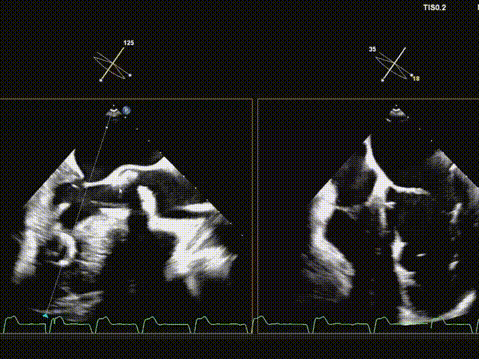

术后超声评估,瓣膜位置深度满意,形态可,微量瓣周漏,最大血流速度1.53m/s,平均跨瓣压差4mmHg。

本例手术的成功实施,标志着武汉亚洲心脏病医院在复杂结构性心脏病介入治疗领域取得了重要进展。面对Type 1型二叶式主动脉瓣重度狭窄合并横位心这一复杂解剖结构,团队通过全超声引导技术,成功实现了“零射线、零造影剂”的绿色介入操作。

华正东教授在术后总结中指出,全超声引导TAVR技术在避免放射线及造影剂相关肾损伤方面具有独特优势,特别适用于合并肾功能不全的高危患者。在本例手术中,超声影像清晰引导了导丝跨瓣、球囊预扩、瓣膜输送与释放等关键步骤,展现了其在复杂解剖条件下实现精准介入的可靠性。

术后超声提示人工瓣膜功能良好,平均跨瓣压差仅4mmHg,血流动力学改善显著。值得一提的是,术中选用的Evolut PRO瓣膜系统凭借其可回收、可重新定位的设计特点,为术中调整释放位置提供了重要技术支持,确保了瓣膜的稳定锚定与功能良好。此例手术的成功,充分展现了全超声引导TAVR在治疗二叶式主动脉瓣狭窄方面的可行性与安全性,为华中地区开展绿色介入技术积累了宝贵经验。